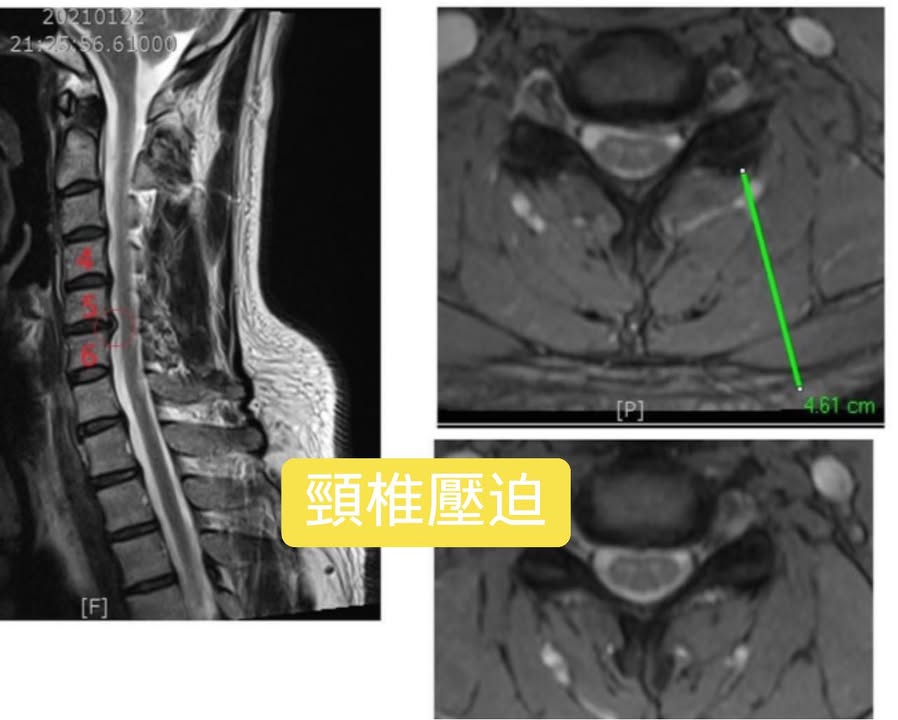

Cervical Spine Treatment Cases 頸椎治療案例 頸椎過直會導致肩膀酸痛嗎?中醫微創針刀療法成功改善頸椎弧度 2021.11.03 頸椎骨刺導致步態不穩、半身麻痛,一定要開刀嗎?中醫針刀治療100天改善實例公開 2021.10.07 冷水刺痛全身、下肢異常竟源自頸椎壓迫?MRI對比揭示非手術療法改善實證 2021.10.08 伏地挺身突然做不到?竟是C6C7頸椎壓迫導致神經肌力減退!中醫微創療法10週改善 2021.09.11 低頭族小心!頸椎滑脫竟導致長期頭痛肩痛與睡眠障礙|12次中醫微創治療成功矯正滑脫 2021.07.16 醫案實證:術後再發的脊髓壓迫症也能靠中醫療法改善 2021.07.10 手術後腳還是麻?頸椎開刀半年症狀未解,靠中醫微創8次改善右腳無力與手麻! 2021.06.30 狂送急診四次竟查不出病因!胸悶心悸原來是頸椎壓迫,靠針刀微創13次改善 2021.06.09 後縱韌帶鈣化壓迫脊髓!步態不穩、手腳麻木竟可逆轉?14週22次針刀治療真實見證 2021.05.06 什麼是中樞型脊髓型頸椎病?症狀、診斷與治療全解析 2021.05.28 神經根型頸椎病症狀解析:肩麻、手痛與肌肉萎縮 2021.04.16 嚴重心悸胸悶竟是頸椎問題!交感神經型頸椎病針治2次症狀明顯改善|真實病例與患者疼... 2021.04.07 從心悸胸悶到手麻夜痛難眠,她竟是頸椎壓迫!真實MRI對比見證中醫逆轉勝療效 2021.04.04 從手腳無力到步態不穩,他竟是頸椎脊髓型壓迫!三個月密集針刀療法逆轉勝|台北蔡大哥... 2021.03.31 頸椎椎間盤突出要一次動四節嗎?手術vs.保守治療完整解析 2021.03.27 ← 上一頁 2 3 4 5 6 下一頁 →